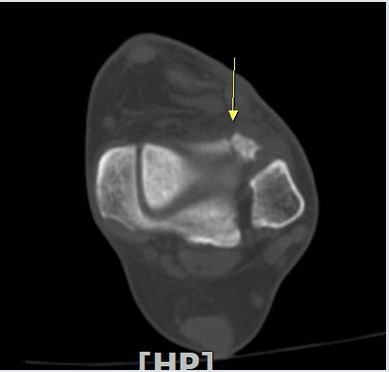

°Ë Ç» ÅÍ ÃÔ ¿µ : ÃÊÀ½ÆÄ°Ë»ç¿¡¼­ °üÂûµÇ´Â  °Íº¸´Ù  ºñ±³Àû  Å«  °ñÆíÀÌ °üÂûµÊ(»çÁø 8, 9, 10).